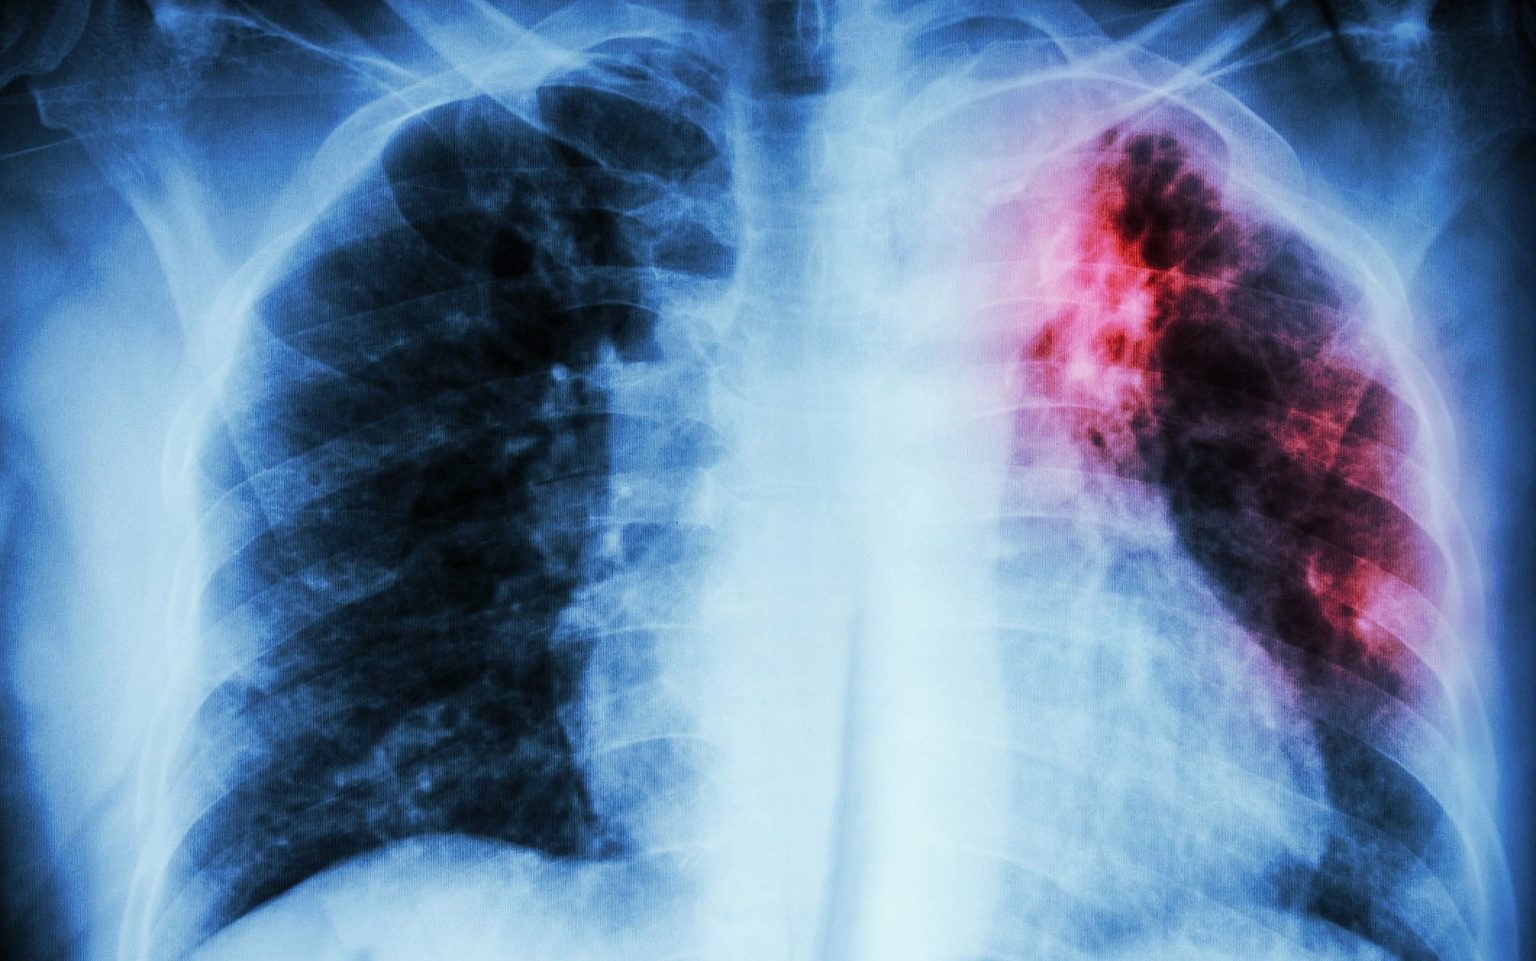

Каждый год 24 марта отмечается Всемирный день борьбы с туберкулезом, призванный повысить осведомленность общественности о губительных последствиях туберкулеза для здоровья, общества и экономики и активизировать усилия по борьбе с глобальной туберкулезной эпидемией.

По данным минздрава в Астраханской области в прошлом году от разных форм туберкулёза погибло почти полторы тысячи человек, что является одним из самых высоких показателей смертности в стране.